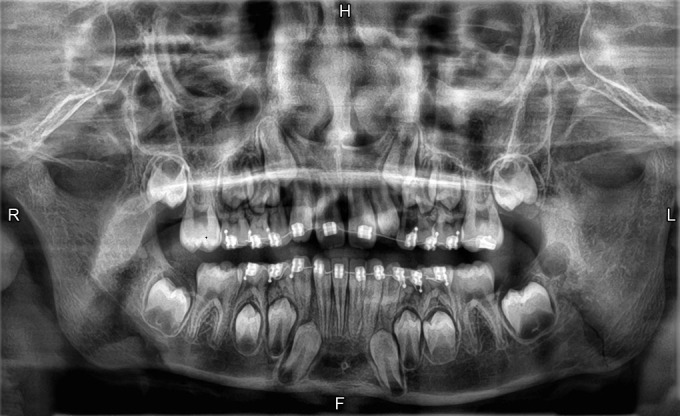

Case description: Three pediatric patients with mandibular fractures were treated using orthodontic appliances for IMF-case 1: a 9-year-old male with a left mandibular angle fracture was treated with stainless steel brackets and elastics for 2 weeks. Follow-up showed full recovery with no pain or occlusal issues. Case 2: a 6-year-old male with bilateral condylar and symphyseal fractures was treated with brackets on all teeth up to the deciduous second molars. After 2 weeks, improved occlusion and mouth opening were noted. Case 3: a 6-year-old female with a right condylar fracture showed improved occlusion and symptom resolution after 2 weeks of treatment.